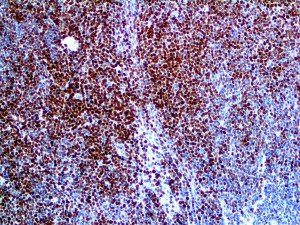

It is the ICU physician who is most likely to witness one of the deadliest manifestations of the abnormal immunological response, the cytokine storm syndrome (CSS). This response is also referred to by some as the cytokine release syndrome (CRS). CSS is characterized by continuous activation and expansion of macrophage and lymphocyte populations, which secrete large amounts of cytokines, causing the cytokine storm. This massive cytokine release is akin to hemophagocytic lymphohistiocytosis (HLH) disease, a syndrome characterized by initial unchecked and persistent activation of cytotoxic T lymphocytes and NK cells.

Clinical and laboratory manifestations of HLH include fever, enlarged liver and/or spleen, neurologic dysfunction, coagulopathy, liver dysfunction, cytopenias (i.e., low levels of erythrocytes, leukocytes, and/or platelets), hypertriglyceridemia, hyperferritinemia, hemophagocytosis, and eventually diminished NK cell activity as the immune system becomes progressively paralyzed. HLH can be familial (primary HLH) or secondary to another disease process (sHLH), such as rheumatic disease, in which it is referred to as macrophage activation syndrome (MAS, characterized by elevated ferritin).